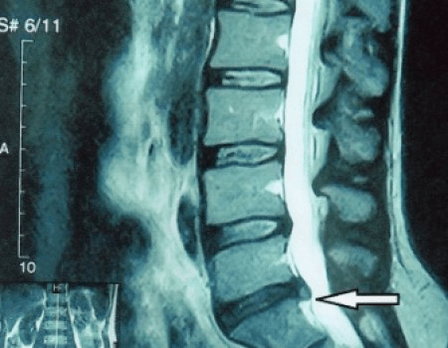

Spinal disc herniation on MRI scan

Why did this happen?Over time, the fiber ring gradually wears out.It can no longer stretch, but protrudes from the disc or breaks.It stops the transfer and transformation of the main vertical load to radial load.With age, stress gradually accumulates inside the discs and their structure changes.If all these processes taken in a separate disk are transferred to the entire spine, then we get a condition called osteochondrosis in the clinic.Now we can start defining.

Since the discs themselves can only be seen using CT or MRI, magnetic resonance and X-ray computed tomography are indicated to clarify the internal structure of cartilage and formations such as protrusions and tears.Thus, with the help of these methods, an accurate diagnosis is made, and the result of the tomography becomes an indication and even an actual guide for the surgical treatment of hernias in the neurosurgery department.

• If you have a hernia, you should monitor it dynamically, conduct regular MRI, do not increase its size or perform modern minimally invasive surgical treatment, because without exception, all conservative methods of treatment of exacerbation of osteochondrosis leave the hernia in place and only relieve temporary symptoms: inflammation, pain, drawing and muscle spasm.